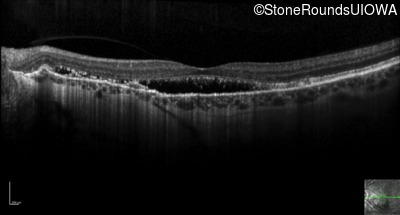

Optical Coherence Tomography - Left - 20/30 -2 sc

Exemplar / OCT Stack

OCT Stack